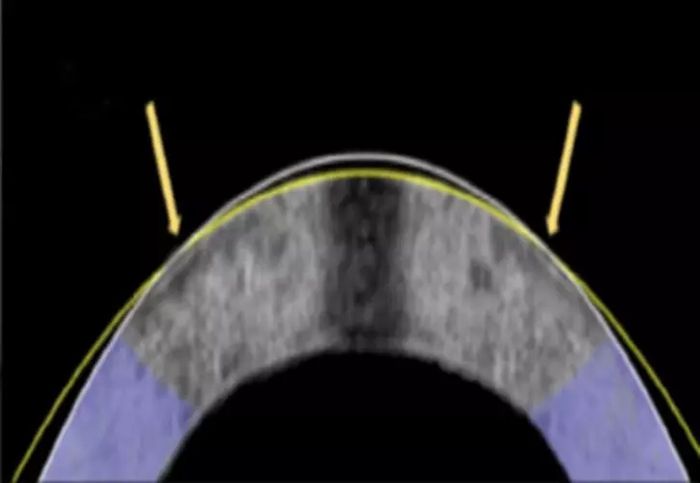

전기기계적 재성형으로 각막이 평평하게 변형됐다. 원래 각막(흰색 선)과 성형 후 각막(노란색 선). 사진=Daniel Kim and Mimi Chen |

연구팀은 백금으로 콘택트렌즈를 제작해 약한 전기 자극을 가해 부드러운 상태로 만든 뒤, 성형되면 전류 공급을 멈췄다. pH가 정상으로 돌아온 뒤에는 각막이 다시 단단해지면서 바뀐 형태를 유지했다.